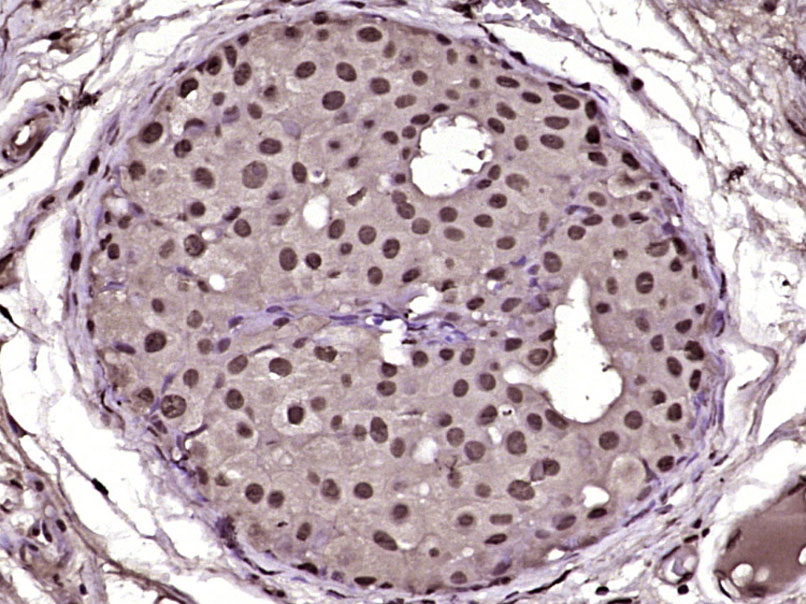

Paraformaldehyde-fixed, paraffin embedded (Human breast carcinoma); Antigen retrieval by boiling in sodium citrate buffer (pH6.0) for 15min; Block endogenous peroxidase by 3% hydrogen peroxide for 20 minutes; Blocking buffer (normal goat serum) at 37°C for 30min; Antibody incubation with (PLK2) Polyclonal Antibody, Unconjugated (bs-12730R) at 1:400 overnight at 4°C, followed by operating according to SP Kit(Rabbit) (sp-0023) instructionsand DAB staining.